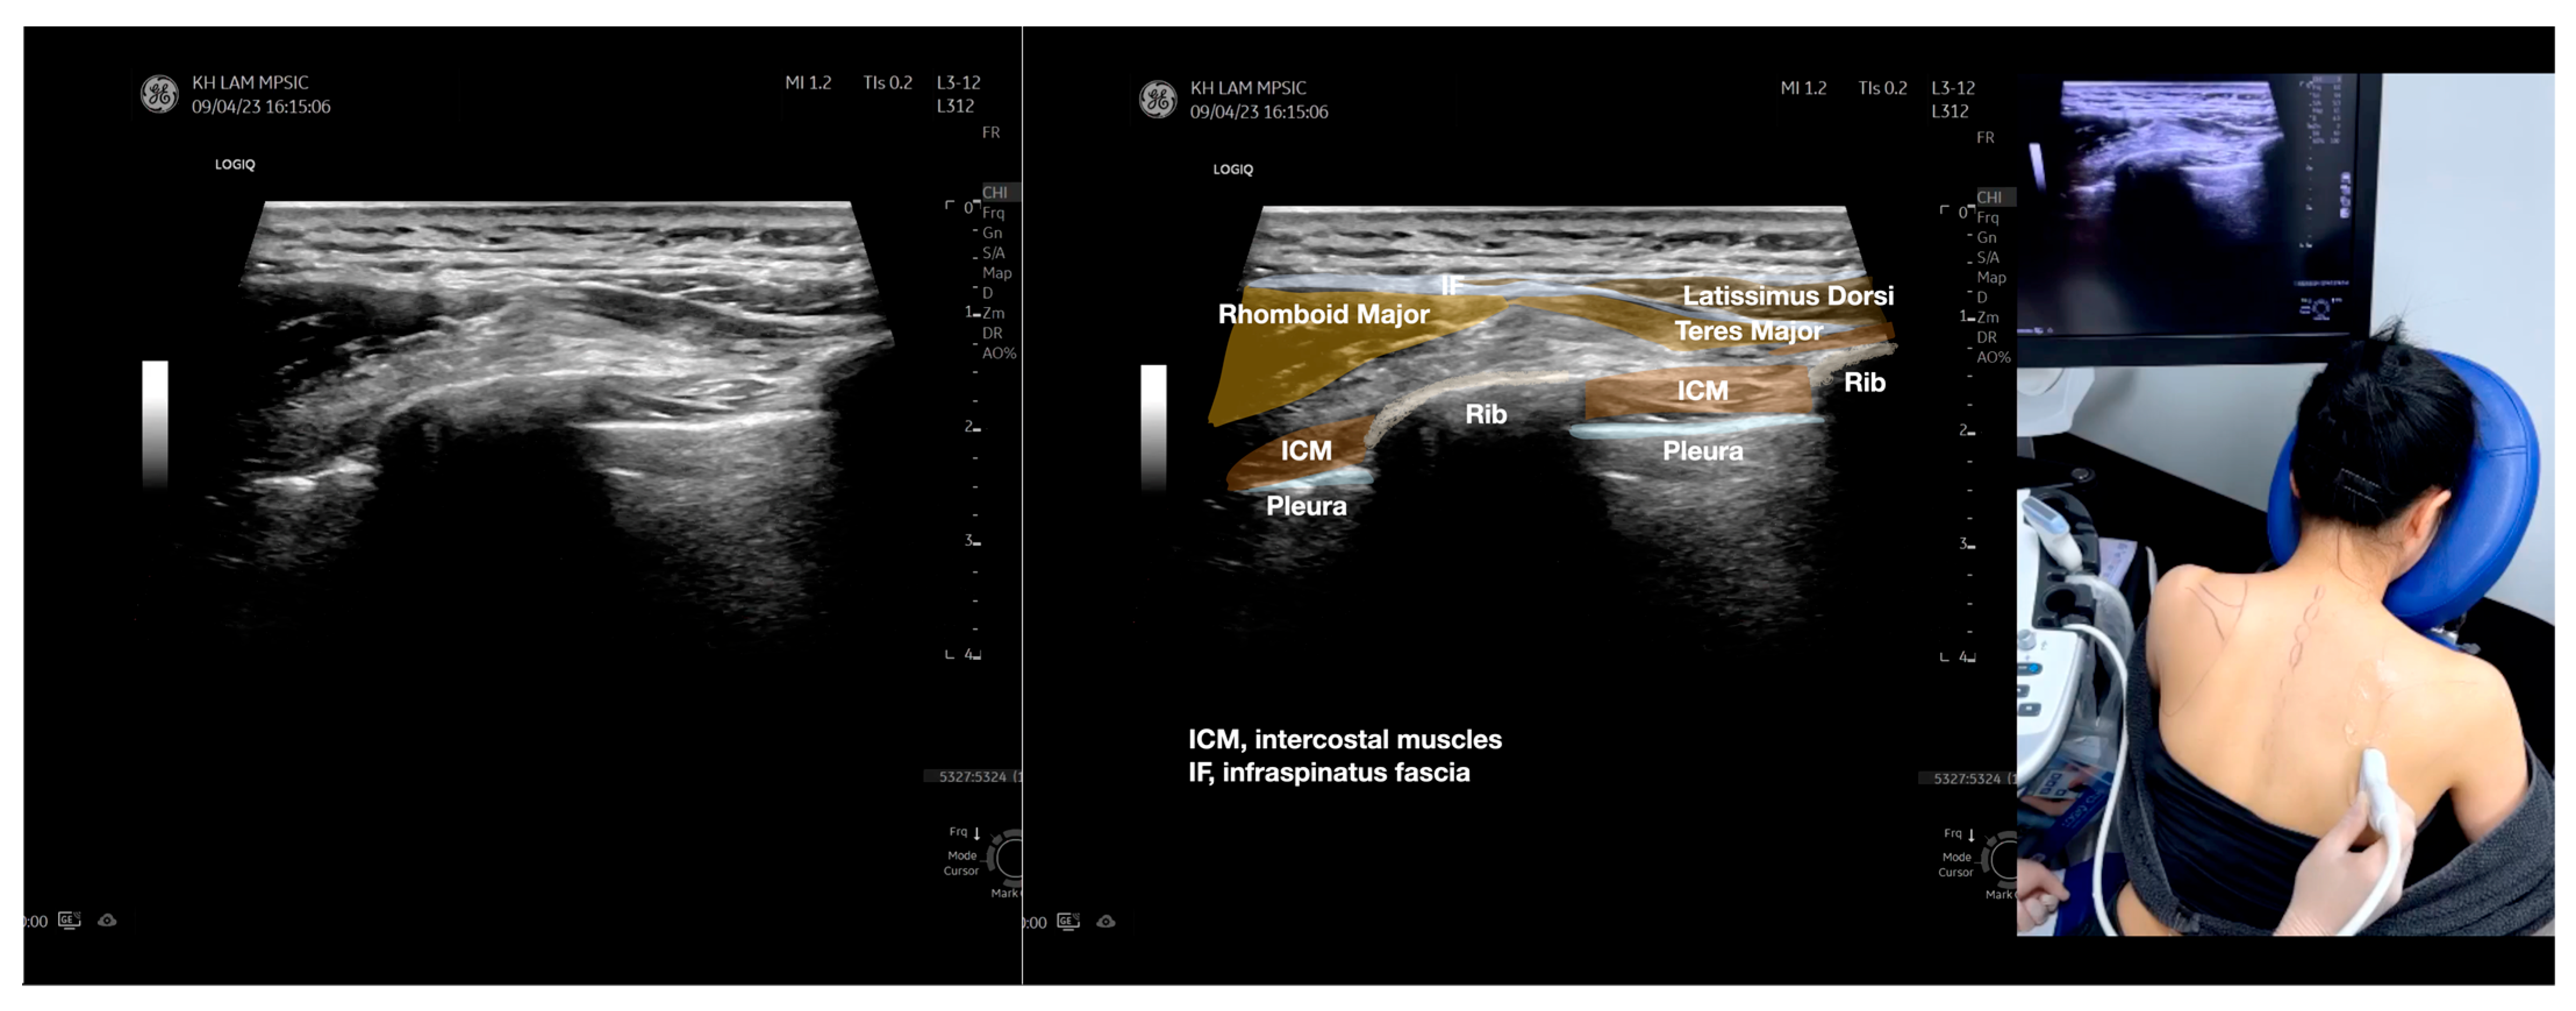

Figure 2.

Sonoanatomy of the lateral border of the inferior trapezius, its related muscles, and the infraspinatus fascia. The step-by-step scanning techniques of the structures illustrated in this figure have been shown in Video S6. Available online: https://www.dropbox.com/s/vjj49wiwdsidouz/Figure%202.docx?dl=0 (accessed on 1 January 2023). Dynamic ultrasound scanning of the anterior shoulder with the humerus externally rotated (palm up), elbow straight, and the shoulder actively flexed and abducted at about 90 to 100 degrees shows that the fibrotic and thickened bursa was noted to be snapping between the subscapularis tendon and the coracoacromial ligament, as shown in Video S3. The patient noticed this snapping during many of his daily activities with his shoulder flexed just above 90 degrees, e.g., taking off clothes and combing hair. Ultrasound-guided injection of the thickened and fibrotic bursa did not reproduce the usual pain nor reduce the pain, and it did not improve the shoulder snapping and flexion power with the elbow straight, shoulder flexed to 90°, and the humerus externally rotated (palm up). Ultrasound-guided injection of the cortical break reproduced the concordant pain and temporarily and partially reduced the pain with snapping and residual anterior shoulder pain (Video S4), but it did not change the snapping or weakness in the right shoulder flexion with the humerus in external rotation. With the failure of direct anterior treatment to the suspected lesions, it was essential to further explore other causes for the anterior painful snapping. Further detailed musculoskeletal examination of the scapular movement showed that the right scapulothoracic movements were not smooth compared to the left counterpart (Video S5) [4,5]. There might be some disruptions in the right infraspinatus fascia (IF) and its related muscles, including the lateral edge of the right inferior trapezius, rhomboid minor and major [6], teres major, latissimus dorsi [7,8] (LD), and posterior deltoid attachments to the IF [9,10]. Clinically, prominent and active trigger points were observed in the right infraspinatus muscle. Holding the inferior angle of the scapula, with the examiner’s fingers, especially over the origin of the teres major muscle over the scapula, the latissimus dorsi [11,12,13] and the scapular insertion of the rhomboid major muscle significantly improved the power of the resisted shoulder flexion with the elbow straight and the shoulder flexed to 90° with the humerus externally rotated (palm up). In order to illustrate the utilization of ultrasound-guided sonopalpation and ultrasound-guided digital palpation for detecting the suspected lesions of the IF and its related muscles, we presented the following videos (Videos S6–S9) and still images (Figure 2, Figure 3, Figure 4 and Figure 5) to demonstrate the essential techniques and crucial points of getting the normal sonoanatomy of the IF and its related structures. The gross anatomy of the IF and its related muscles were also shown in Figure 6, Figure 7 and Figure 8.